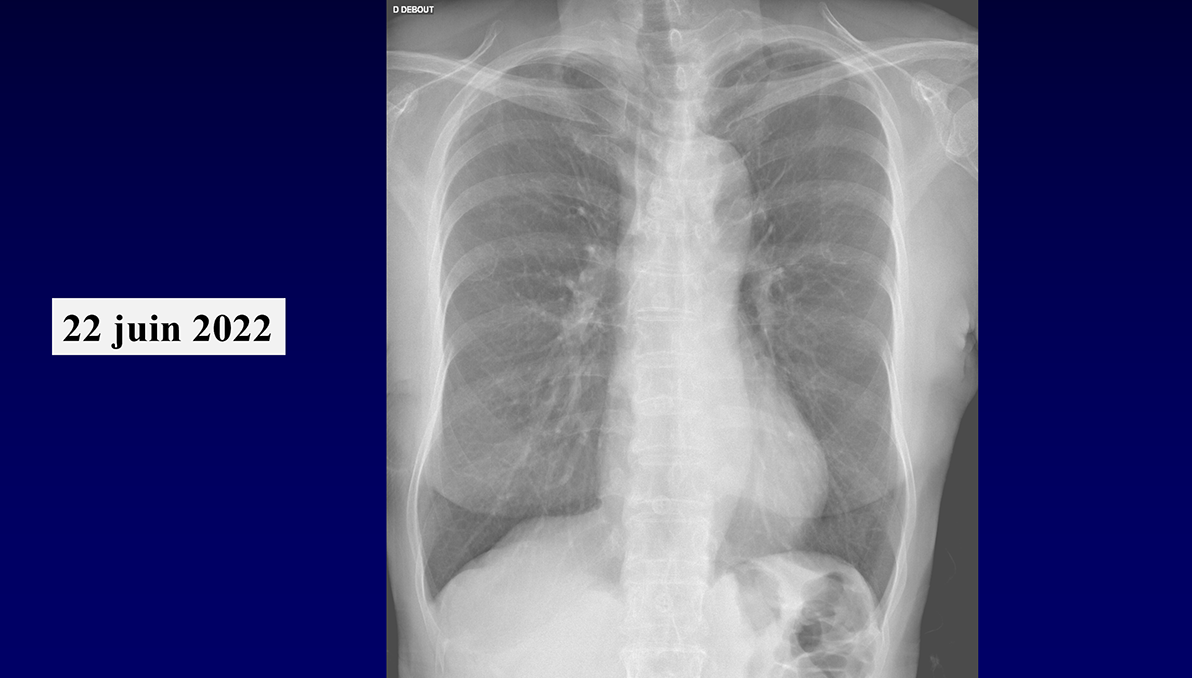

QUIZ N° 013*

Homme de 70 ans

QUEL EST VOTRE DIAGNOSTIC ?

Quel est le mécanisme le plus probable de cette pathologie ?